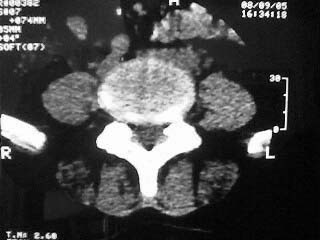

标题: CT15786:腰痛,腿麻三个月

f,64。腰痛,腿麻三个月

是黄韧带钙化吗

腰椎退行性变;黄韧带钙化。

黄韧带增厚钙化

也可以是小关节增生所致.